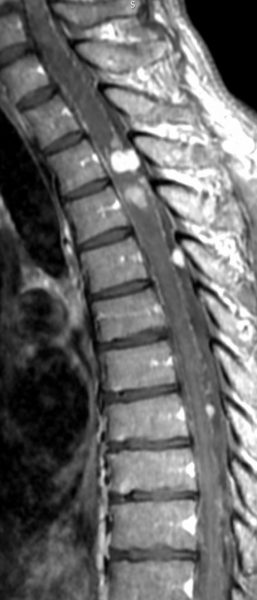

フォン・ヒッペル・リンドウ病の患者さんの脊髄(胸髄)にできた血管芽腫です。上下の脊髄が腫れたり,脊髄の中に空洞(腫瘍のう胞あるいは脊髄空洞症といいます)ができます。 手術治療は症状が出るまで,あるいは症状がかなり強くなってからしかしません。なぜなら,たくさんできる(多発)することが多くて,複数回の手術になってしまうこともあるからです。手術をするたびに,四肢のしびれや麻痺などの後遺症がのこる可能性もあるので,この手術は,脊髄腫瘍の手術経験が相当にたくさんある脳外科医にしかできません。